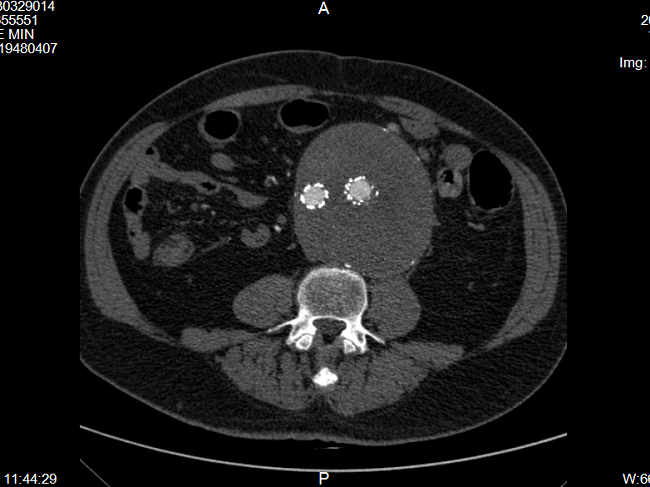

74岁的郭大爷,7年前发现腹主动脉瘤,在郑州大学第五附属医院血管外科成功行腹主动脉瘤腔内修复术(Endovascular Aneurysm Repair,EVAR),术后的第7年,在医院住院做常规复查,经使用增强CT检查(CTA)后显示:腹主动脉瘤体增大,再次形成“定时炸弹”(图1)。郭大爷精神状况较好,无腹胀腹痛、头晕头痛等不适,但瘤体明显增大,瘤腔内存在血流信号,考虑EVAR术后Ⅱ型内漏,随时可能再次破裂,手术迫在眉睫。

▲图1 腹主动脉瘤腔内修复术后Ⅱ型内漏,增大的瘤体